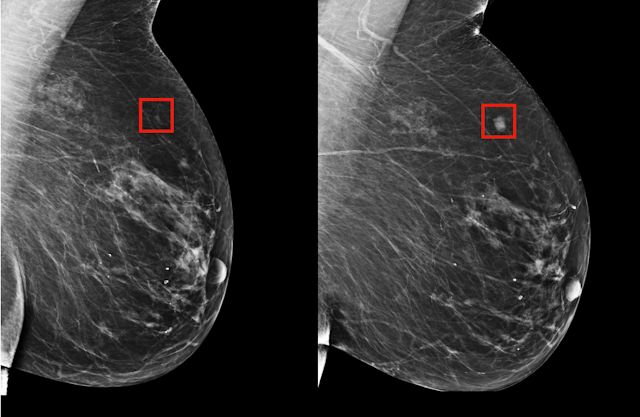

Mammograms, which provide X-ray images of breast tissue, are an invaluable screening tool to detect early stage breast cancer. While mammograms can detect abnormalities that would otherwise remain undetected through physical exam alone - including small tumors not easily visible through physical inspection alone - their success in early cancer detection depends on a number of factors:

Tumor Size: Mammography can detect tumors as small as 2-3 millimeters in diameter; many stage 1 breast cancers fall within this size range and thus become detectable via mammography.

Breast Density: Breast density can differ considerably between individuals, making mammography harder to interpret in some instances due to dense breast tissue density. Therefore, additional imaging methods like ultrasound or MRI may be recommended in such instances for greater detection accuracy of small tumors on mammograms.